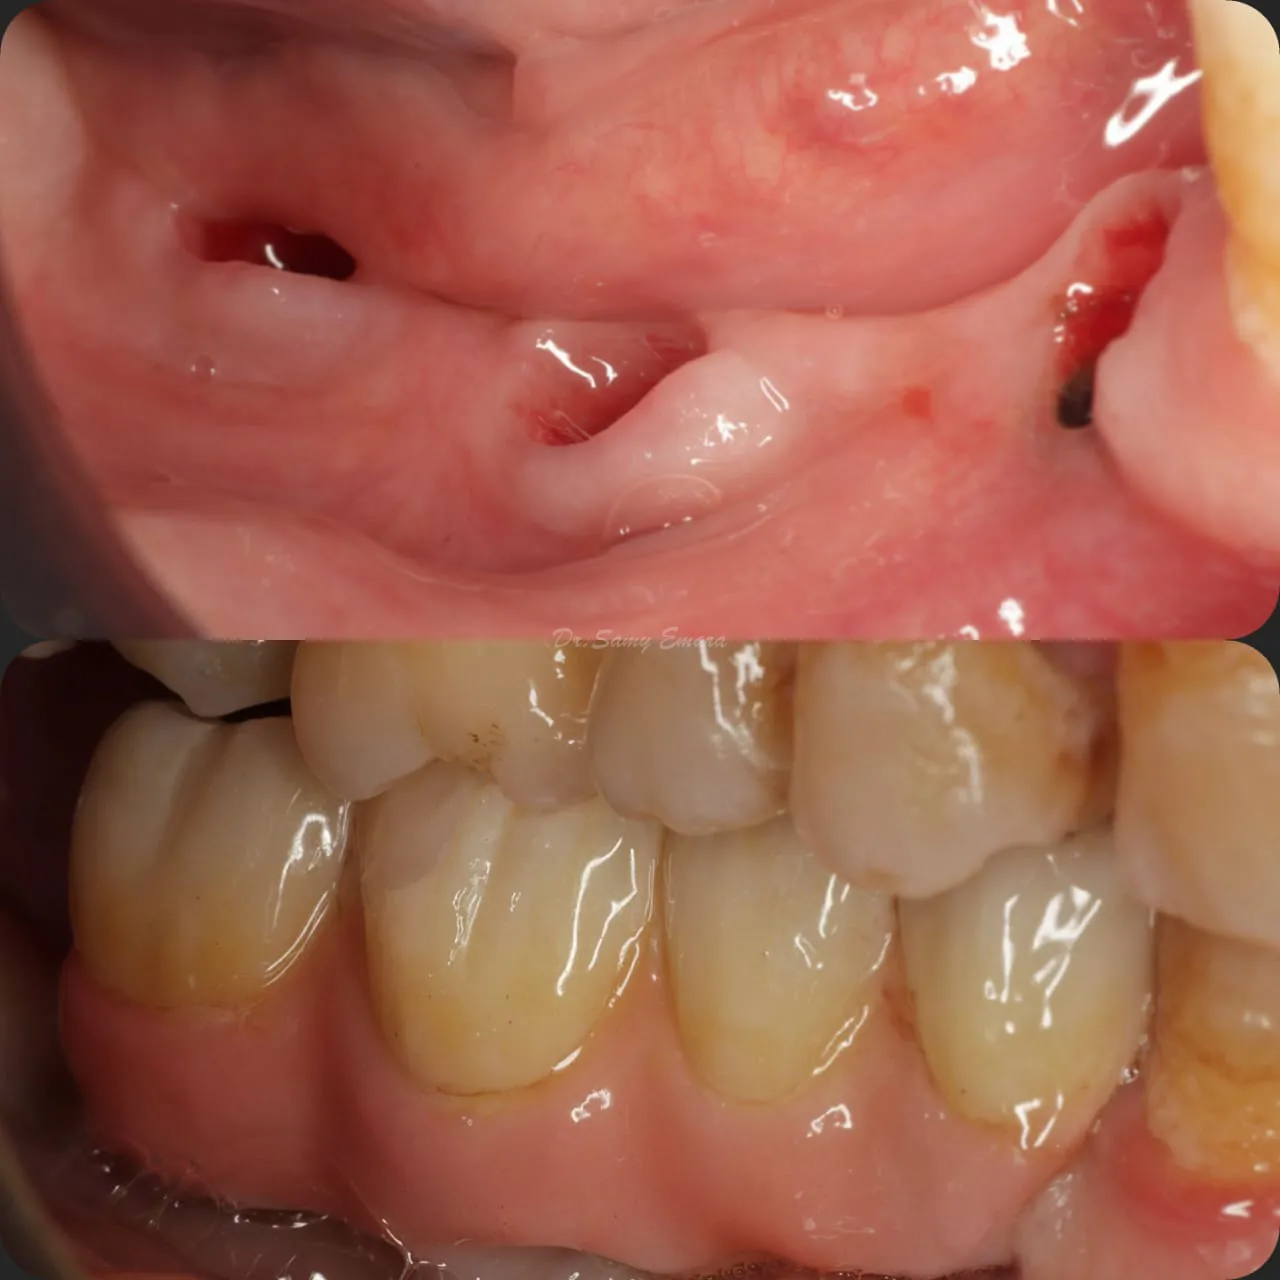

Implant